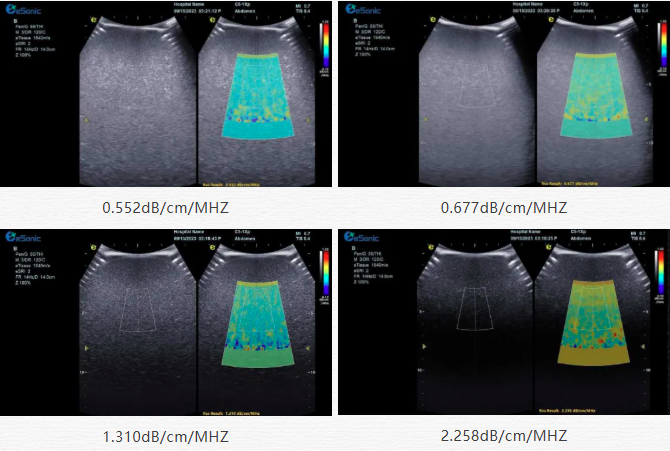

该技术基于声波在介质传播时的衰减,衰减由声吸收、反射、散射及波束扩散所致,声衰减系数(α,单位 dB/cm?MHz,与超声频率和传播距离成正比)可通过测定同频超声波在组织中的衰减程度,借回波信号分析预测声衰减系数或衰减率来评估组织特性。

目前市面常用瞬时弹性成像或仿体参照法,存在适用性、准确性差及无衰减图局限。hjc888黄金城官网则采用准确度更高的 ALA 幅度损失衰减法,超声波深度传播时回波幅度渐降,其对数与深度有良好线性关系,声衰减量与传播衰减系数成函数关系,调节取样框大小位置可实时得样框内组织衰减系数,用于定量评估病变程度。